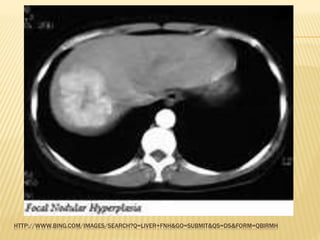

FOCAL NODULAR HYPERPLASIA (FNH)

 It is a focal overgrowth of functioning liver tissue

supported by fibrous stroma

 Usually middle-aged women

 US helps to diagnose but may not be able to

discriminate

 Contrast CT/MRI may show central scarring &

well-vascularized lesion

 FNH contains both hepatocytes & Kupffer cells

 A sulphur colloid liver scan may be useful, since

Kupffer cells take up the colloid

 Does not have malignant potential

 If diagnosis is confirm, no treatment is required

HTTP://WWW.BING.COM/IMAGES/SEARCH?Q=LIVER+FNH&GO=SUBMIT&QS=DS&FORM=QBIRMH